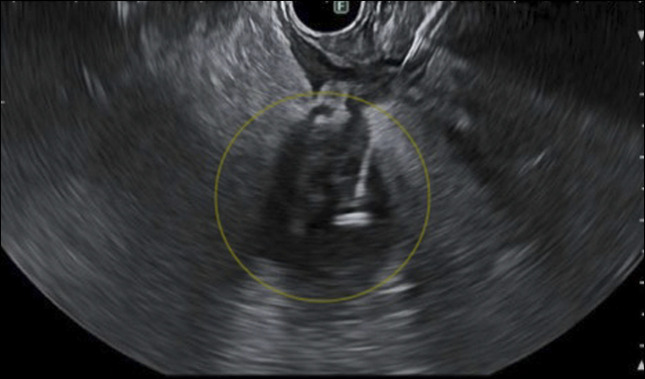

Vermiform appendiceal cancers are rare and commonly diagnosed incidentally after appendectomy for acute appendicitis. Establishing a diagnosis and staging appendiceal cancer is important as the treatment options differ based on the subtypes of tumor and their spread in the peritoneum. The role of endosonography in tissue diagnosis of appendiceal cancer is limited. Most cases are diagnosed and staged radiologically and surgically. Tissue diagnosis is key in management, especially when diagnosis is unclear by other modalities. We report a case of transduodenal endoscopic ultrasound-guided biopsy of an appendiceal lesion, which had significant impact on patient outcome.